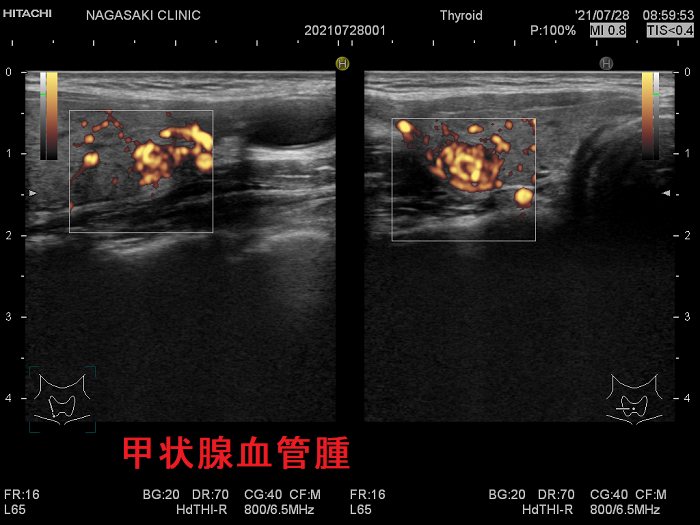

甲状腺に発生する血管腫は非常に稀で、日本の報告例もわずかです(日臨外会誌 72(3),579―583,2011)。

ケース①

ケース②

ケース③

甲状腺血管腫(拡大) ドプラーモード(eFlow);腫瘍内血管が3次元的に見え、毛玉の様。

ケース④